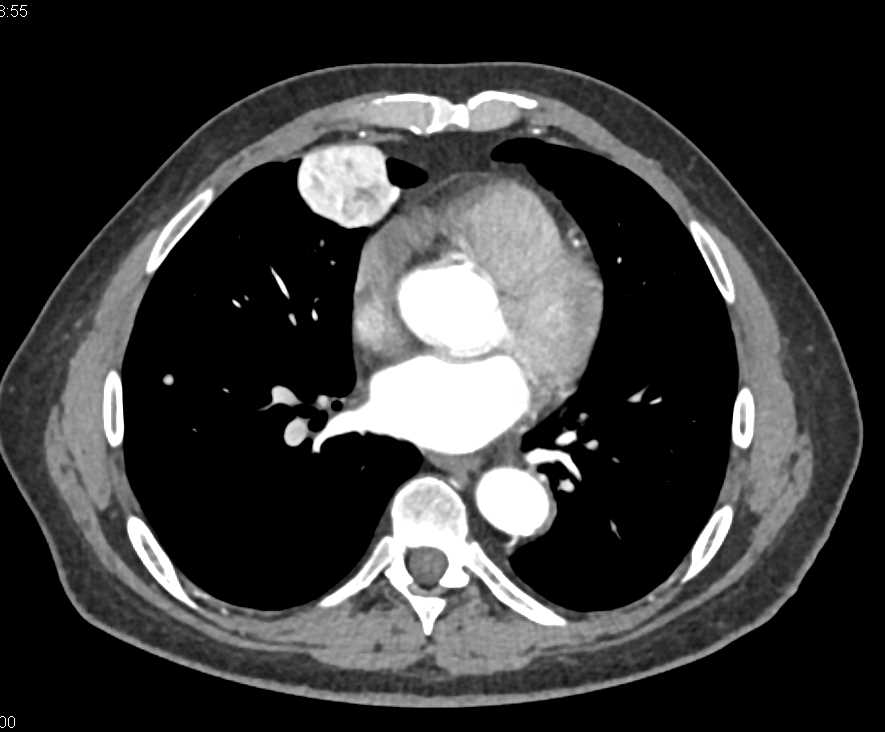

Endovascular Stent Repair with Cinematic Rendering